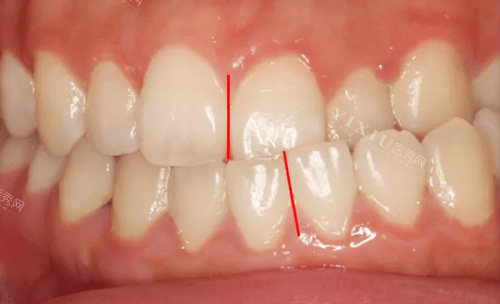

何锦泉医生是广州广大口腔医院的颌面整形医师,拥有丰富的正颌手术经验。他专注于骨性地包天、凸嘴、偏颌等复杂颌面畸形的矫正,尤其擅长运用3D导板技术进行精细手术。3D导板技术通过术前CT扫描建模,模拟截骨范围和骨骼移动轨迹,误差可控制在0.1毫米以内。这种技术不仅提高了手术的精细度,还降低了术后并发症的风险。

何锦泉医生为张先生进行了详细的面部检查和三维模型分析,发现其凸嘴主要是由于上颌骨前突所致。于是,何医生制定了上颌骨后移的手术方案,并结合3D导板技术进行精细定位。

手术中,何锦泉医生利用3D导板技术,精细地将张先生的上颌骨后移到了正常位置。整个手术过程出血量较少,仅约50ml,远低于传统手术。手术完成后,张先生被送入术后复苏室,接受ERAS(加速外科)护理体系的照护。

精细截骨:误差控制在0.1毫米以内,避免传统手术的“一刀切”弊端。